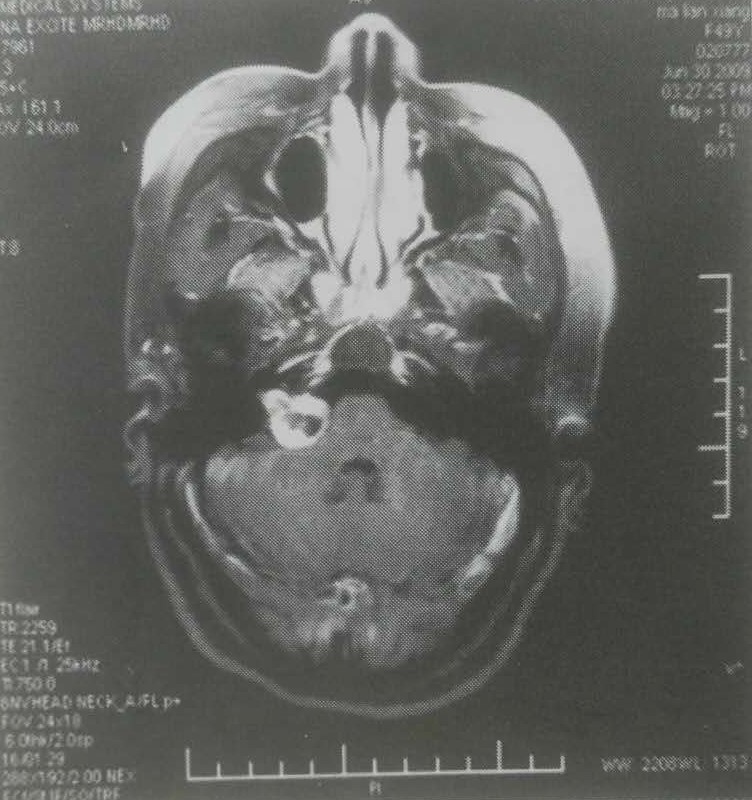

马某,男,59岁。左侧面部麻木,舌部感觉减退2个月,于2001年8月行开颅左侧听神经瘤切除术。2006年3月行伽马刀治疗,如下图:

50%等剂量曲线包饶肿瘤边缘,边缘剂量14Gy,中心剂量28Gy。2009年2月复查患者症状好转,MRI显示肿瘤体积缩小,特别是囊性部分缩小明显,如下图: